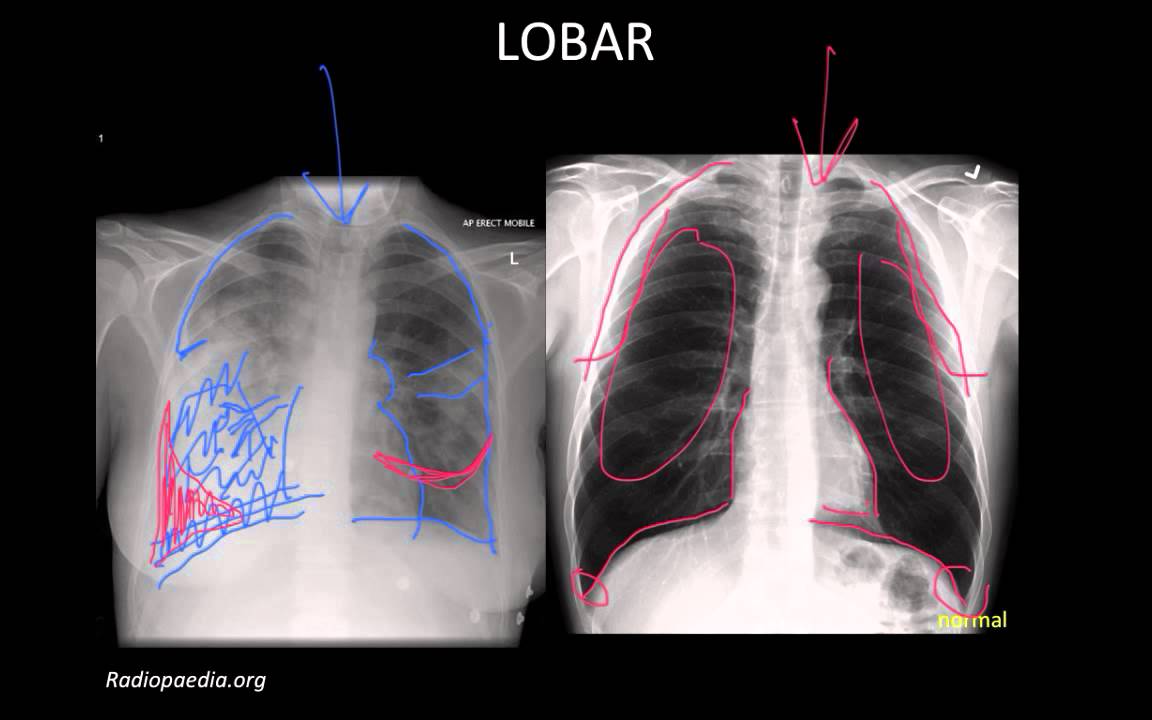

W zapaleniu płuc na zdjęciu RTG nacieki różnią się od raka czy obrzęku serca dynamiką – powtarzane zdjęcia po 24-48 godzinach pokazują ewolucję, np. zanik konsolidacji po antybiotyku w 70% przypadków bakteryjnych (dane z Polish Journal of Radiology, 2021). Interstycjalne zapalenie płuc cechują drobne, siateczkowate zacienienia rozlane obustronnie, w czasie gdy lobarne – ostre granice z granicą anatomiczną płata. Radiolog interpretuje „zagadki” jak znak sylwetki pnia oskrzelowego („drzewo oskrzelowe”) czy air bronchogram – powietrzne oskrzela w zacienionym tle, typowe dla konsolidacji. Effuzja opłucnowa towarzyszy w 30% przypadków, tworząc zacienienie w zatokie żebrowo-przeponowej.

Konsolidacja płucna, czyli konsolidacja płucna, stanowi podstawowy objaw i pojawia się jako jednorodne zacienienie zajmujące segment lub płat płuca. Na zdjęciu RTG widać wyraźne granice zmian, często z powietrznym bronchogramem – czarnymi oskrzelami na tle białego tła. W zapaleniu bakteryjnym, np. pneumokokowyminfiltraty są lobarne i zajmują dolne płaty w 70-80% przypadków. Zapalenie płuc na zdjęciu rentgenowskim może imitować atelektazę, ale obecność gorączki i leukocytozy pomaga w różnicowaniu.

Wirusowe zapalenia płuc pokazują obraz drzewa w pączku, z centralnym zagęszczeniem i otaczającymi go pasmami nacieków. Drobne guzki pęcherzykowe tworzą mozaikowy wzór, szczególnie w zapaleniu wywołanym Mycoplasma. Śródmiąższowe zapalenie objawia się liniami Kerleya lub siateczkowatym zagęszczeniem, bez dużych konsolidacji.